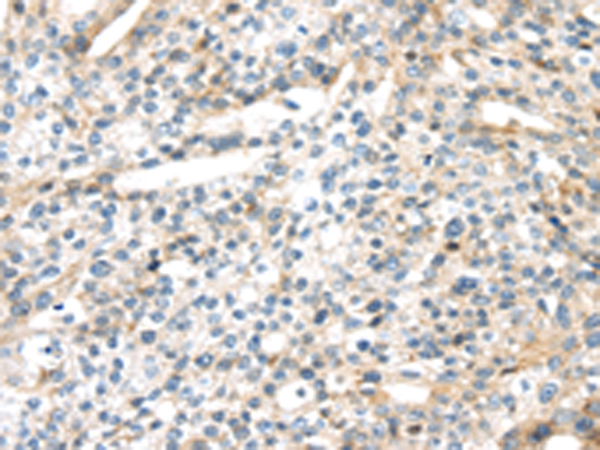

分类: 科研抗体货号: P08885别名: MSP; MSPL; MSPS; TMPRSS11应用: IHC反应种属: Human, Mouse